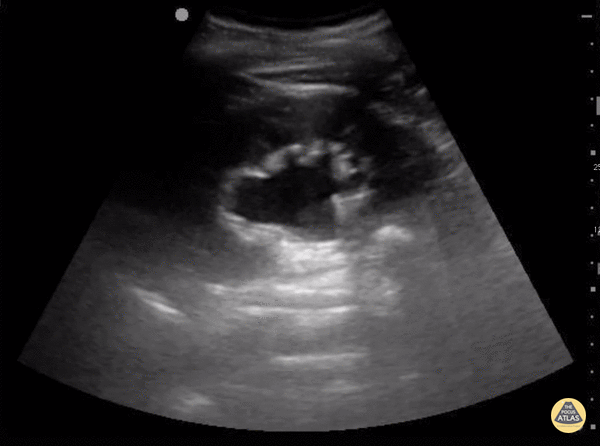

![]()

Hydronéphrose légère. © POCUS Atlas